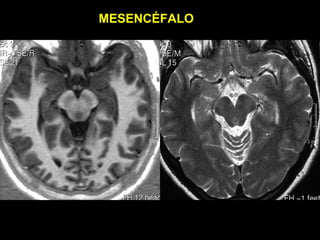

MESENCÉFALO

COLÍCULOS

SUPERIORES

INFERIORES

• TETO MESENCEFÁLICO (LÂMINA QUADRIGEMINAL)

SUBSTÂNCIA

CINZA

PERI-

AQUEDUTAL

NIGRA/

NÚCLEOS

RUBRO

• MESENCÉFALO

• PEDÚNCULOS CEREBRAIS

(SUBST. NIGRA)

• TETO MESENCEFÁLICO

(COLÍCULOS INFERIORES)

• CISTERNAS

• INTERPEDUNCULAR

• QUADRIGEMINAL

• PERIMESENCEFÁLICA

•   IV PAR CRANIANO (DECUSSAÇÃO)

•   AQUEDUTO DE SYLVIUS

•   SUBSTÂNCIA CINZENTA PERIAQUEDUTAL

•   ARTÉRIAS CEREBRAIS POSTERIORES

• PEDÚNCULOS

– NÚCLEOS RUBOS

– SUBST. NIGRA

• TETO - COLÍCULOS SUPERIORES

• INTERPEDUCULAR

• PERIMESENCÉFALICA

• AMBIENS